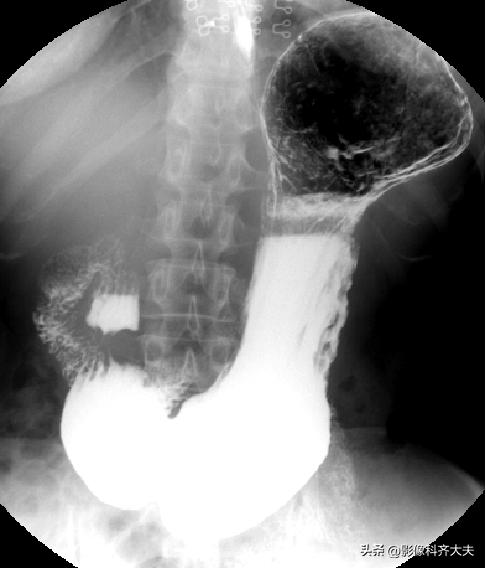

全胃充盈相(站立位)

- 全胃充盈相(半卧位、立位)